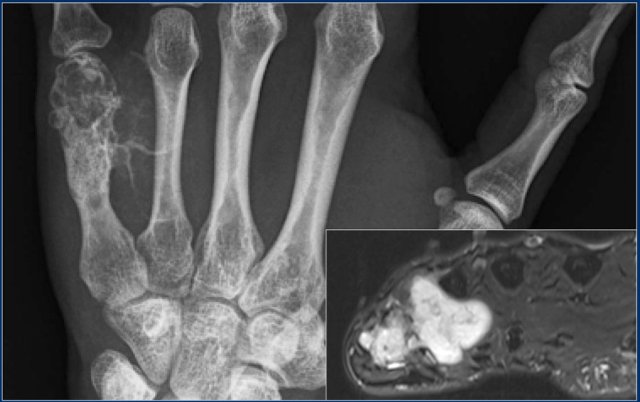

Here a 44-year old male with a mixed lytic and sclerotic mass arising from the fifth metacarpal bone.

There are calcified strands within the soft tissues.

T2-weighted axial MR image demonstrates high signal intensity of the tumor in the metacarpal bone with extension of a lobulated soft tissue mass.

Diagnosis: chondrosarcoma grade 2